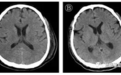

治疗96小时后(起病第14天),患者出现颌面及口角频繁抽搐,伴持续呃逆,医生查体发现颈抵抗阳性,双侧瞳孔等大等圆,对光反射迟钝,四肢肌张力升高,双侧膝反射亢进,双侧巴氏征及踝阵挛阳性,头颅CT颅内未见异常,测脑脊液压力大于330mmH2O,脑脊液外观无色清亮,生化检测无异常。

北京地坛医院重症医学科、检验科及中国疾控中心传染病所联合工作组对采集的脑脊液标本进行宏基因组二代测序、鉴定可能的感染病原体过程中,排除了其他病原体,获得了新冠病毒基因组序列。通过基因测序证实脑脊液中存在新冠病毒,临床诊断病毒性脑炎。

随后,医护人员经过对其14天机械通气和甘露醇控制颅压、咪唑安定控制抽搐、丙种球蛋白及甲基强的松龙抗炎等针对病毒性脑炎的处理,观察患者肺病影像学逐渐好转,神经系统症状消失。